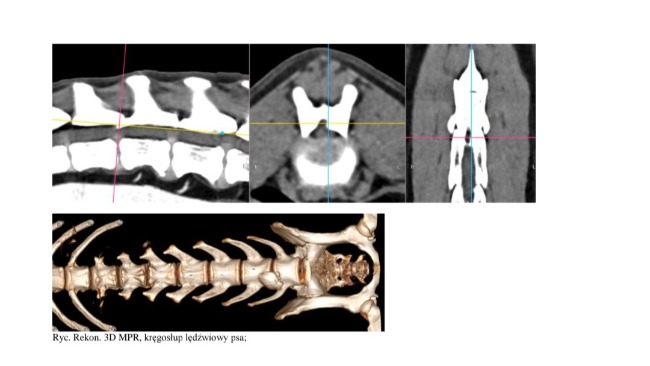

Pod koniec października Magnus miał robione TK (tomografię komputerową) - głównie kręgosłupa, ze względu na spondylozę na odcinku L6-L7, ale też ponownie, kontrolnie prześwietliliśmy stawy (przód i tył).

Ze względu na spondylozę terapię IRAP chcę zastosować również do kręgosłupa (niechirurgiczna metoda leczenia zwyrodnień i stanów zapalnych kręgosłupa).

•Konsultacja ortopedyczna kontrolna, badania, TK + pierwsze osocze podane w Krakowie - 3700 zł

•IRAP - podanie do kręgosłupa, odcinek L6-L7 - również około 1000 zł